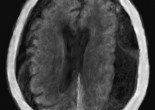

Hématome sous-dural aigu et chronique

L’hématome sous dural est la constitution d’une poche de sang dans l’espace sous dural, en dessous de la dure-mère, le feuillet le plus externe et le plus dur des méninges … Lire la suite